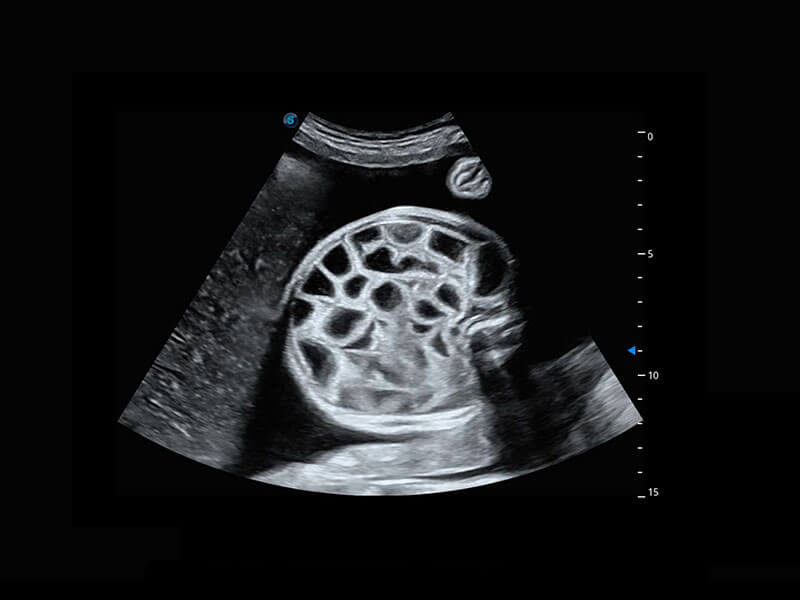

胎心筛查

P60搭载一系列胎儿心脏成像技术,实现精细的胎儿心脏评估。

• 四腔切面

• 四腔心血流

• 右室双出口

• 胎心容积成像